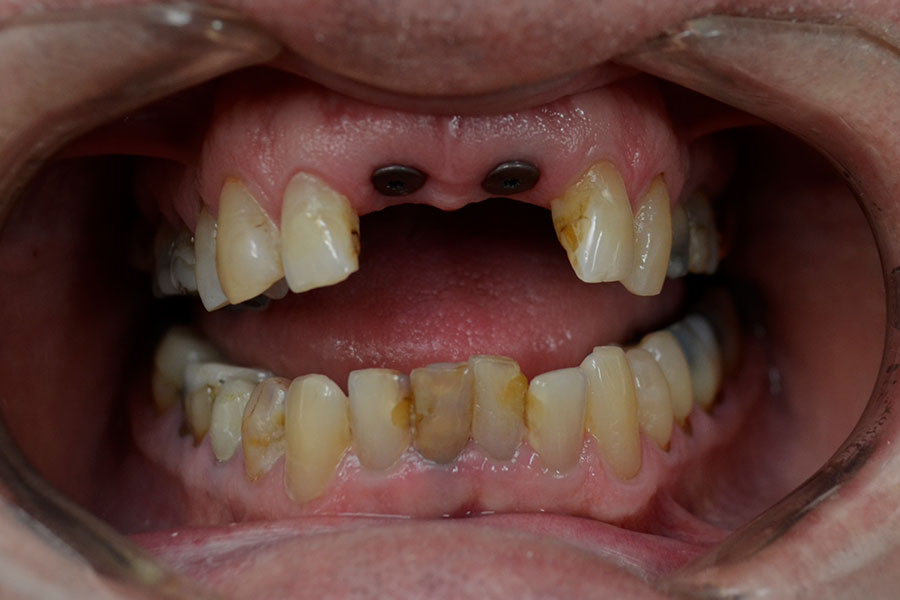

Nic lost two front teeth while playing football about 40 years ago.

He wore a removable metal partial denture. These teeth were finally restored with two dental implants to support the teeth individually.